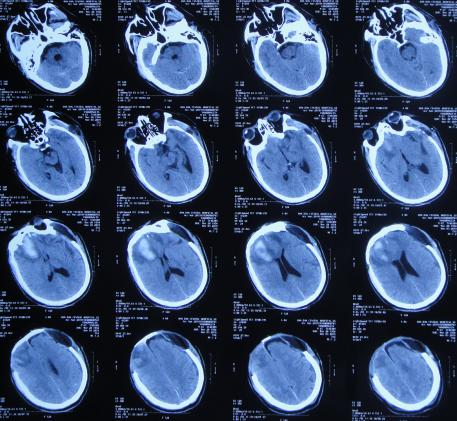

但颅骨修补术+脑室腹腔分流术后第5天即2019年12月18日,出现意识有点不清。

颅骨修补术+脑室腹腔分流术后第6天即2019年12月19日,复查头颅CT示引流管周围少量出血( 图-16 ),给予拔除头部引流,换做腰大池引流。

图-16: 2019年12月19日头颅CT

腰大池引流术后5天即2019年12月24日(颅骨修补术后11天即拔除脑室引流管后5天),查头颅CT示脑室仍扩张( 图-17 )。

图-17: 2019年12月24日头颅CT

腰大池引流术后8天即2019年12月27日(颅骨修补术后11天即拔除脑室引流管后8天),查头颅CT示脑室有缩小,积血减少( 图-18 )。

图-18: 2019年12月27日头颅CT

腰大池引流术后11天即2019年12月30日(颅骨修补术后11天即拔除脑室引流管后11天),查头颅CT示仍有脑室扩张( 图-19 )。

图-19: 2019年12月30日头颅CT

腰大池引流后13天即2020年1月1日,复查头颅CT( 图-20 )示认为积血基本吸收;给予拔除腰大池引流管。

图-20: 2020年1月1日头颅CT

但拔除腰大池引流管后第2天就出现了发热,再次给予腰大池引流,但引流出淡红色浑浊脑脊液,且化验脑脊液示白细胞高,考虑颅内感染,脑脊液培养无细菌生长,给予抗菌素后3天后体温变正常。

第2次腰穿引流后11天即2020年1月14日,查头颅CT( 图-21 )后认为病情有好转,随后拔除腰大池引流管,计划明日第2次进行脑室腹腔分流术。

图-21: 2020年1月14日头颅CT

颅骨修补术后33天即第1次脑室分流管拔除后27天2020年1月15日,进行了第2次的脑室腹腔分流术( 图-22 )。

图-22: 2020年1月15日头颅CT

颅骨修补术后35天即第2次脑室腹腔分流术后2天2020年1月17日,病情稳定,查头颅CT( 图-23 )后认为无异常。

图-23: 2020年1月17日头颅CT

颅骨修补术后40天即第2次脑室腹腔分流术后7天即2020年1月22日(第2家医院住院治疗43天)出院,转住入第3家的北京某康复医院进行康复治疗。

在第3家医院康复治疗近1个月时间内,曾4次查头颅影像(2020年1月22日( 图-24 )、2020年1月29日( 图-25 )、2020年2月10日( 图-26 )、2020年2月19日( 图-27 ))均示脑室仍有扩张,但未给予特殊处理。

图-24: 2020年1月22日头颅核磁

图-25: 2020年1月29日头颅CT

图-26: 2020年2月10日头颅CT

图-27: 2020年2月19日头颅CT

但住院期间间断性发热仅给予药物后仍反复,且大小便时有*禁失**,因此于第3家医院治疗28天后即2020年2月19日,转回当地的第4家河北省邯郸市某三甲医院治疗。

在第4家医院治疗26天,仍间断性发热、大小便*禁失**加重,住院期间曾2次查头颅CT(2020年2月27日( 图-28 )、2020年3月12日( 图-29 ))示脑室仍扩张。

图-28: 2020年2月27日头颅CT

图-29: 2020年3月12日头颅CT

治疗期间给予抗生素,并多次腰椎穿刺,脑脊液培养示无菌,发热虽有好转但大小便*禁失**无改善,且意识变模糊。经当地医生介绍转住入北京北亚骨科医院的李小勇脑脊液科。